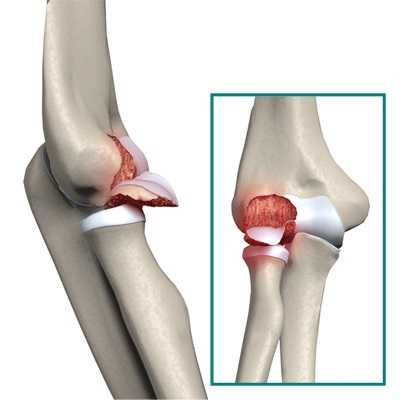

Анатомия перелома локтевого отростка

Перелом локтевого отростка происходит в основном при падении на локоть с высоты собственного роста. Существуют случаи, когда данному перелому характерен вариант со смещением. Чаще всего он происходит на уровне верхушки отростка, но иногда несет за собой внесуставное повреждение. Именно к этому участку крепится сухожилие трехглавой мышцы плеча (трицепса), которое “тянет” отломанные элементы проксимально (в сторону плеча), тем самым создавая диастаз промежуток между отломками, что является серьезным препятствием для сращения перелома.

Локтевой отросток — это верхний конец локтевой кости, участвующий в образовании локтевого сустава.

Локтевой отросток расположен непосредственно под кожей и таким образом практически не защищен мышцами или другими мягкими тканями. Перелом локтевого отростка может произойти в результате прямого удара в эту область, например, при падении. Перелом характеризуется выраженным болевым синдромом и в значительной степени ограничивает движения в локтевом суставе либо делает их практически невозможными.

Локтевой отросток — это костный выступ на задней поверхности локтевого сустава.

- Локтевой отросток — часть локтевой кости, чашеобразно охватывающая нижний конец плеча и формирующая шарнир для движений в локтевом суставе. Локтевой отросток хорошо пальпируется под кожей, поскольку покрыт лишь тонким слоем мягких тканей.